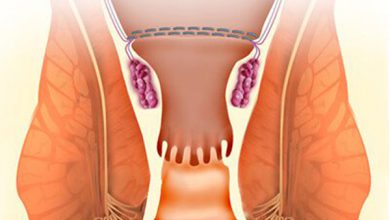

لایه نازک و همرنگ دندان که جهت رفع مشکلات ظاهری و بهبود زیبایی لبخند، روی سطح دندانها قرار میگیرد لمینت دندان نام دارد. با قرارگیری لمینت روی سطح دندانها،مشکلات ظاهری دندان از جمله طرح، شکل، رنگ و اندازه دندان به وضعیت دلخواه شما در میآید. البته به یاد داشته باشید که لمینت علاوه بر مزایای زیبایی، موجب افزایش مقاومت و قدرت دندانها میشود. بدین منظور باید به یک متخصص لمینت دندان مراجعه نموده و ضمن سنجش دقیق میزان آسیب دیدگی دندانها، پس از طراحی لبخند فرآیند لمینت گذاری دندانها انجام شود. در اینصورت دندانهای محکم، بادوام و طرح لبخند زیبایی خواهید داشت.

امروزه لمینتهای دندانی با توجه به کاربردهای فراوانی که دارند، موجب رفع مشکلات دندان و بهبود طرح لبخند افراد شده است. بعضی از مهمترین کاربردهای لمینت دندان عبارت است از:

1- شکستگی دندانها

3- ترکخوردگی دندان

3- کجی و بدشکلی دندان